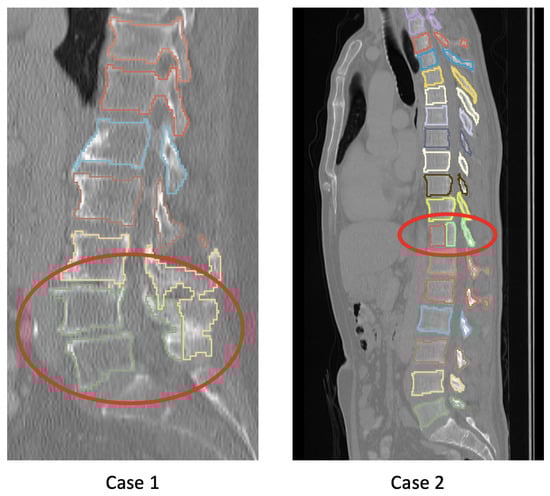

5. Discussion

5.1. Segmentation Performance

5.2. Current Limitations and Future Work